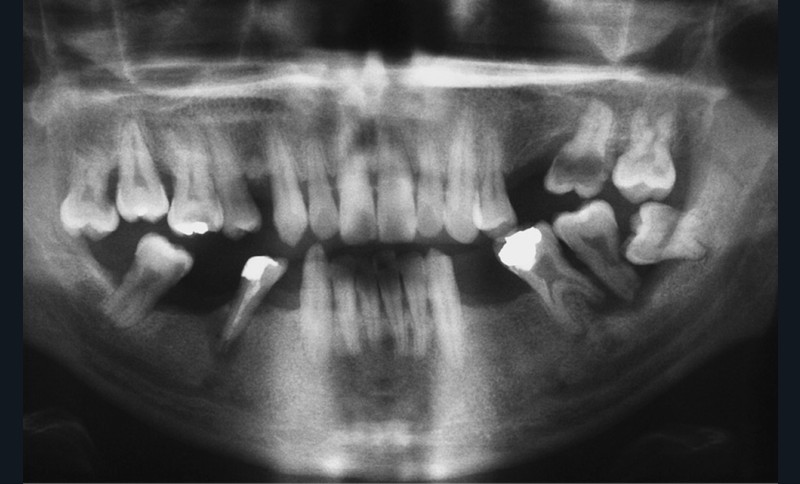

L’obésité, définie par un indice de masse corporelle (IMC) ≥ 30 kg/m2, est une maladie inflammatoire chronique complexe et multifactorielle caractérisée par un dépôt excessif de graisse dans le tissu adipeux. Selon l’OMS, depuis 1975, le nombre de cas d’obésité a presque triplé à l’échelle planétaire [1]. En 2020, près d’un Français sur deux était en surpoids, tandis que 17 % étaient obèses [2]. Or l’obésité est responsable d’une haute mortalité à l’échelle mondiale et est un facteur de risque majeur pour de nombreuses maladies, dont les maladies cardiovasculaires, le diabète de type 2 et certains cancers [1]. Son impact sur la santé des populations et son coût économique et social sont donc considérables. Ces deux dernières décennies, de nombreuses études ont montré que l’obésité pouvait aussi être incriminée dans la détérioration de la santé bucco-dentaire [3] (fig. 1 à 7).